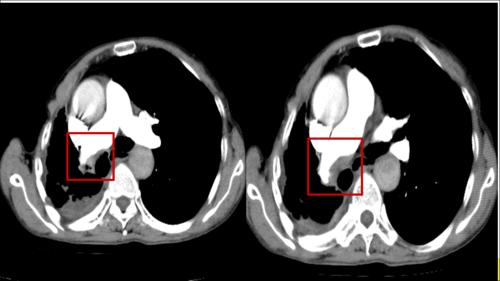

正常肺CT肺窗示意图

正常肺CT肺窗示意图,正常肺CT肺窗示意图